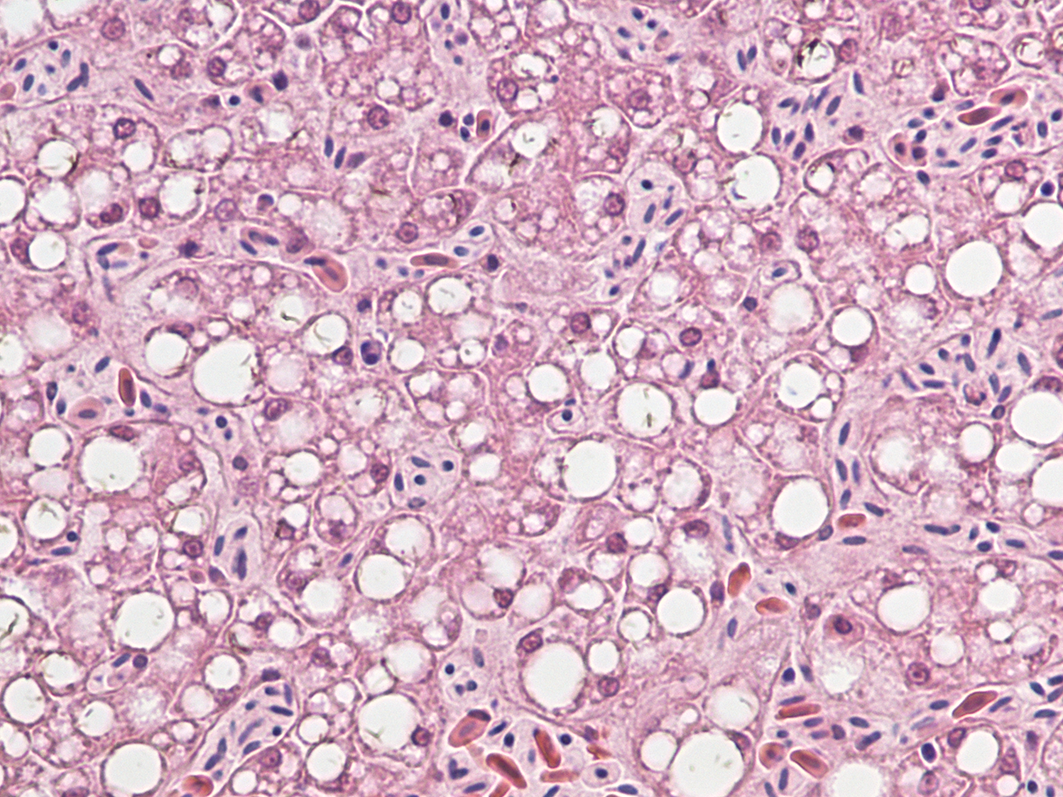

A microscopic image of a liver from a bald eagle that died from Wisconsin River Eagle Syndrome. The large white spaces demonstrate tissue damage characteristic of the disease. Photo by Marie Pinkerton

Researchers suspected the disease was related to a virus because results from necropsies of eagles with Wisconsin River Eagle Syndrome found liver and brain damage, but no connection to environmental toxins.

“One of the things that struck us right away is that this (virus) is actually a relative of the human hepatitis C virus,” Goldberg said. “Which was suggestive because hepatitis C … causes hepatitis in humans — liver damage. And we were seeing liver damage in these eagles.”